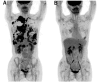

Case report: A patient with breast cancer with extensive metastases to the liver, lymph nodes, pleura and bones was diagnosed using [18F]fluorodeoxyglucose positron emission tomography (FDG-PET). The patient was immediately started on systemic drug therapy with tamoxifen and leuprorelin, but it failed to suppress the tumor. Then, combination treatment with radiation, immunotherapy with biological response modifier (BRM)-activated killer (BAK), a low-methionine diet, and o-rMETase was started as second-line treatment. Five months after beginning of the combination treatment, the patient had a subsequent FDG-PET scan and extensive eradication of almost all metastases was observed, with only a metastasis remaining in the liver.